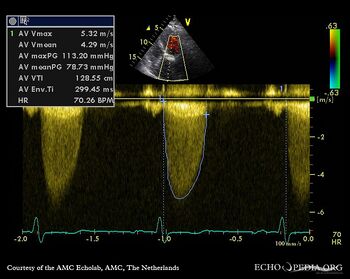

Aortic valve stenosis

J. Vleugels, AMC, The Netherlands